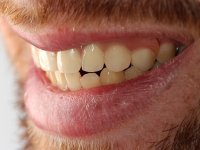

Rehabilitation of the anterior maxilla following traumatic injury in a car accident.

Male patient, 22 years old, non-smoker, appear in our dental office 6 months after a car accident where he lost teeth 21, 22, 23 and 24. Teeth 12 and 11 present mobility grade III, thus with a prognosis of extraction. The gengiva architecture of the edentulous area presents a recession and a flat surface.